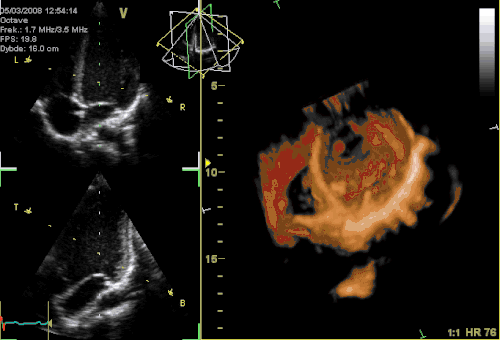

Кардиология, сосудистая и кардиохирургия

Эхокардиография (ЭхоКГ) — это ультразвуковая диагностика заболеваний сердца. В этом исследовании оцениваются размеры сердца и его отдельных структур (желудочки, предсердия, межжелудочковая перегородка, толщина миокарда желудочков, предсердий и т. д.), наличие и объём жидкости в полости перикарда, состояние клапанов сердца, а также, в доплеровском режиме, кровоток в сердце и магистральных сосудах. С помощью специальных расчетов и измерений эхокардиография позволяет определять массу миокарда, сократительную способность сердца (фракцию выброса, сердечный выброс и др.). Обычно ЭхоКГ проводится через грудную клетку (трансторакально), также существует чреспищеводная ЭхоКГ (ЧП-ЭхоКГ), когда специальный эндоскопический датчик помещается в пищевод. ЧП-ЭхоКГ позволяет лучше рассмотреть сердце, так как датчик располагается к сердцу ближе, чем при обычной ЭхоКГ и поэтому становится возможным использовать датчик с более высокой частотой ультразвука, что повышает разрешающую способность изображения. Также существуют специальные высокочастотные интраоперационные датчики, которые помогают во время операций на сердце.

4D-ЭхоКГ представленная на изображении, позволяет получать живое 3D-изображение сердца, то есть в реальном времени, что может быть также полезно, для проведения данной методики требуется специальный 4D-датчик.